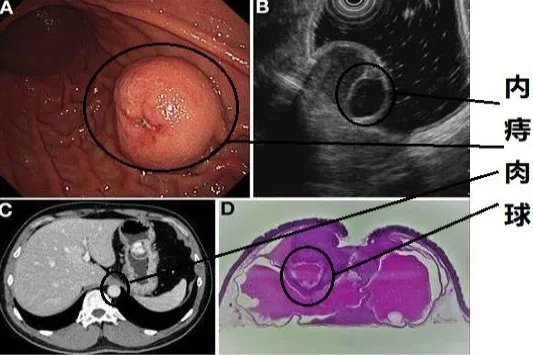

血吸虫通常会导致患者出现发热、全身皮疹、腹痛、腹泻、肝区压痛等症状,出现以上症状时,需要及时去医院就诊,进行血常规、粪便检查、免疫学、CT等检查来确诊。确诊后可遵医嘱使用吡喹酮片、蒿甲醚片等药物进行治疗,也可以通过手术将虫体取出。